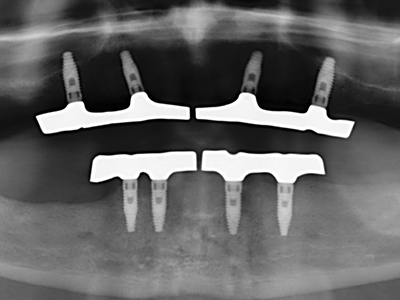

En la extracción de bloques óseos la piezocirugía también presenta ventajas adicionales: Además de la alta precisión en la osteotomía que ya se ha descrito antes, se ha comprobado que el uso de los delgados insertos de sierra resulta especialmente cuidadosas con el hueso. Frente a esto, sobre todo cuando se usan las fresas de Lindemann, cabe esperar pérdidas en la extracción significativamente más altas debido al mayor grosor de la parte frontal del cabezal (Lakshmiganthan, Gokulanathan et al. 2012). La separación basal que se necesita en particular en los injertos de bloque extraídos de forma retromolar se ve facilitada mediante sierras perpendiculares especialmente previstas a tal fin, lo que permite considerar que la cirugía piezoeléctrica es un procedimiento preciso y seguro para la obtención de bloques de hueso en el área retromolar (Happe 2007) (fig. 1-12).

Como ya se ha demostrado en el pasado, básicamente cualquier procedimiento de cirugía de hueso representa una posible indicación para la cirugía piezoeléctrica. Así, la preparación del segmento móvil en la osteogénesis de distracción (fig. 23-25) y en la osteotomía de sándwich puede realizarse con piezas especiales, sin poner en peligro el suministro sanguíneo de la parte crestal, que resulta esencial para el éxito de ambas técnicas (González-García, Diniz-Freitas et al. 2008).

Para la extracción de implantes es posible realizar la preparación de una tapa ósea vestibular que, tras retirar el tornillo del implante, vuelve a fijarse y, de este modo, mantiene el contorno de la apófisis alveolar.

En la cirugía del seno maxilar surgen otros campos de aplicación: En este punto, tras la preparación concéntrica de una tapa ósea de la pared del seno maxilar (que suele tener forma trapezoidal), es posible eliminar patologías y cuerpos extraños del seno maxilar. La tapa ósea se repone después de finalizar la parte intra-antral de la operación y se asegura frente a una posible dislocación mediante cuñas o suturas adaptables.